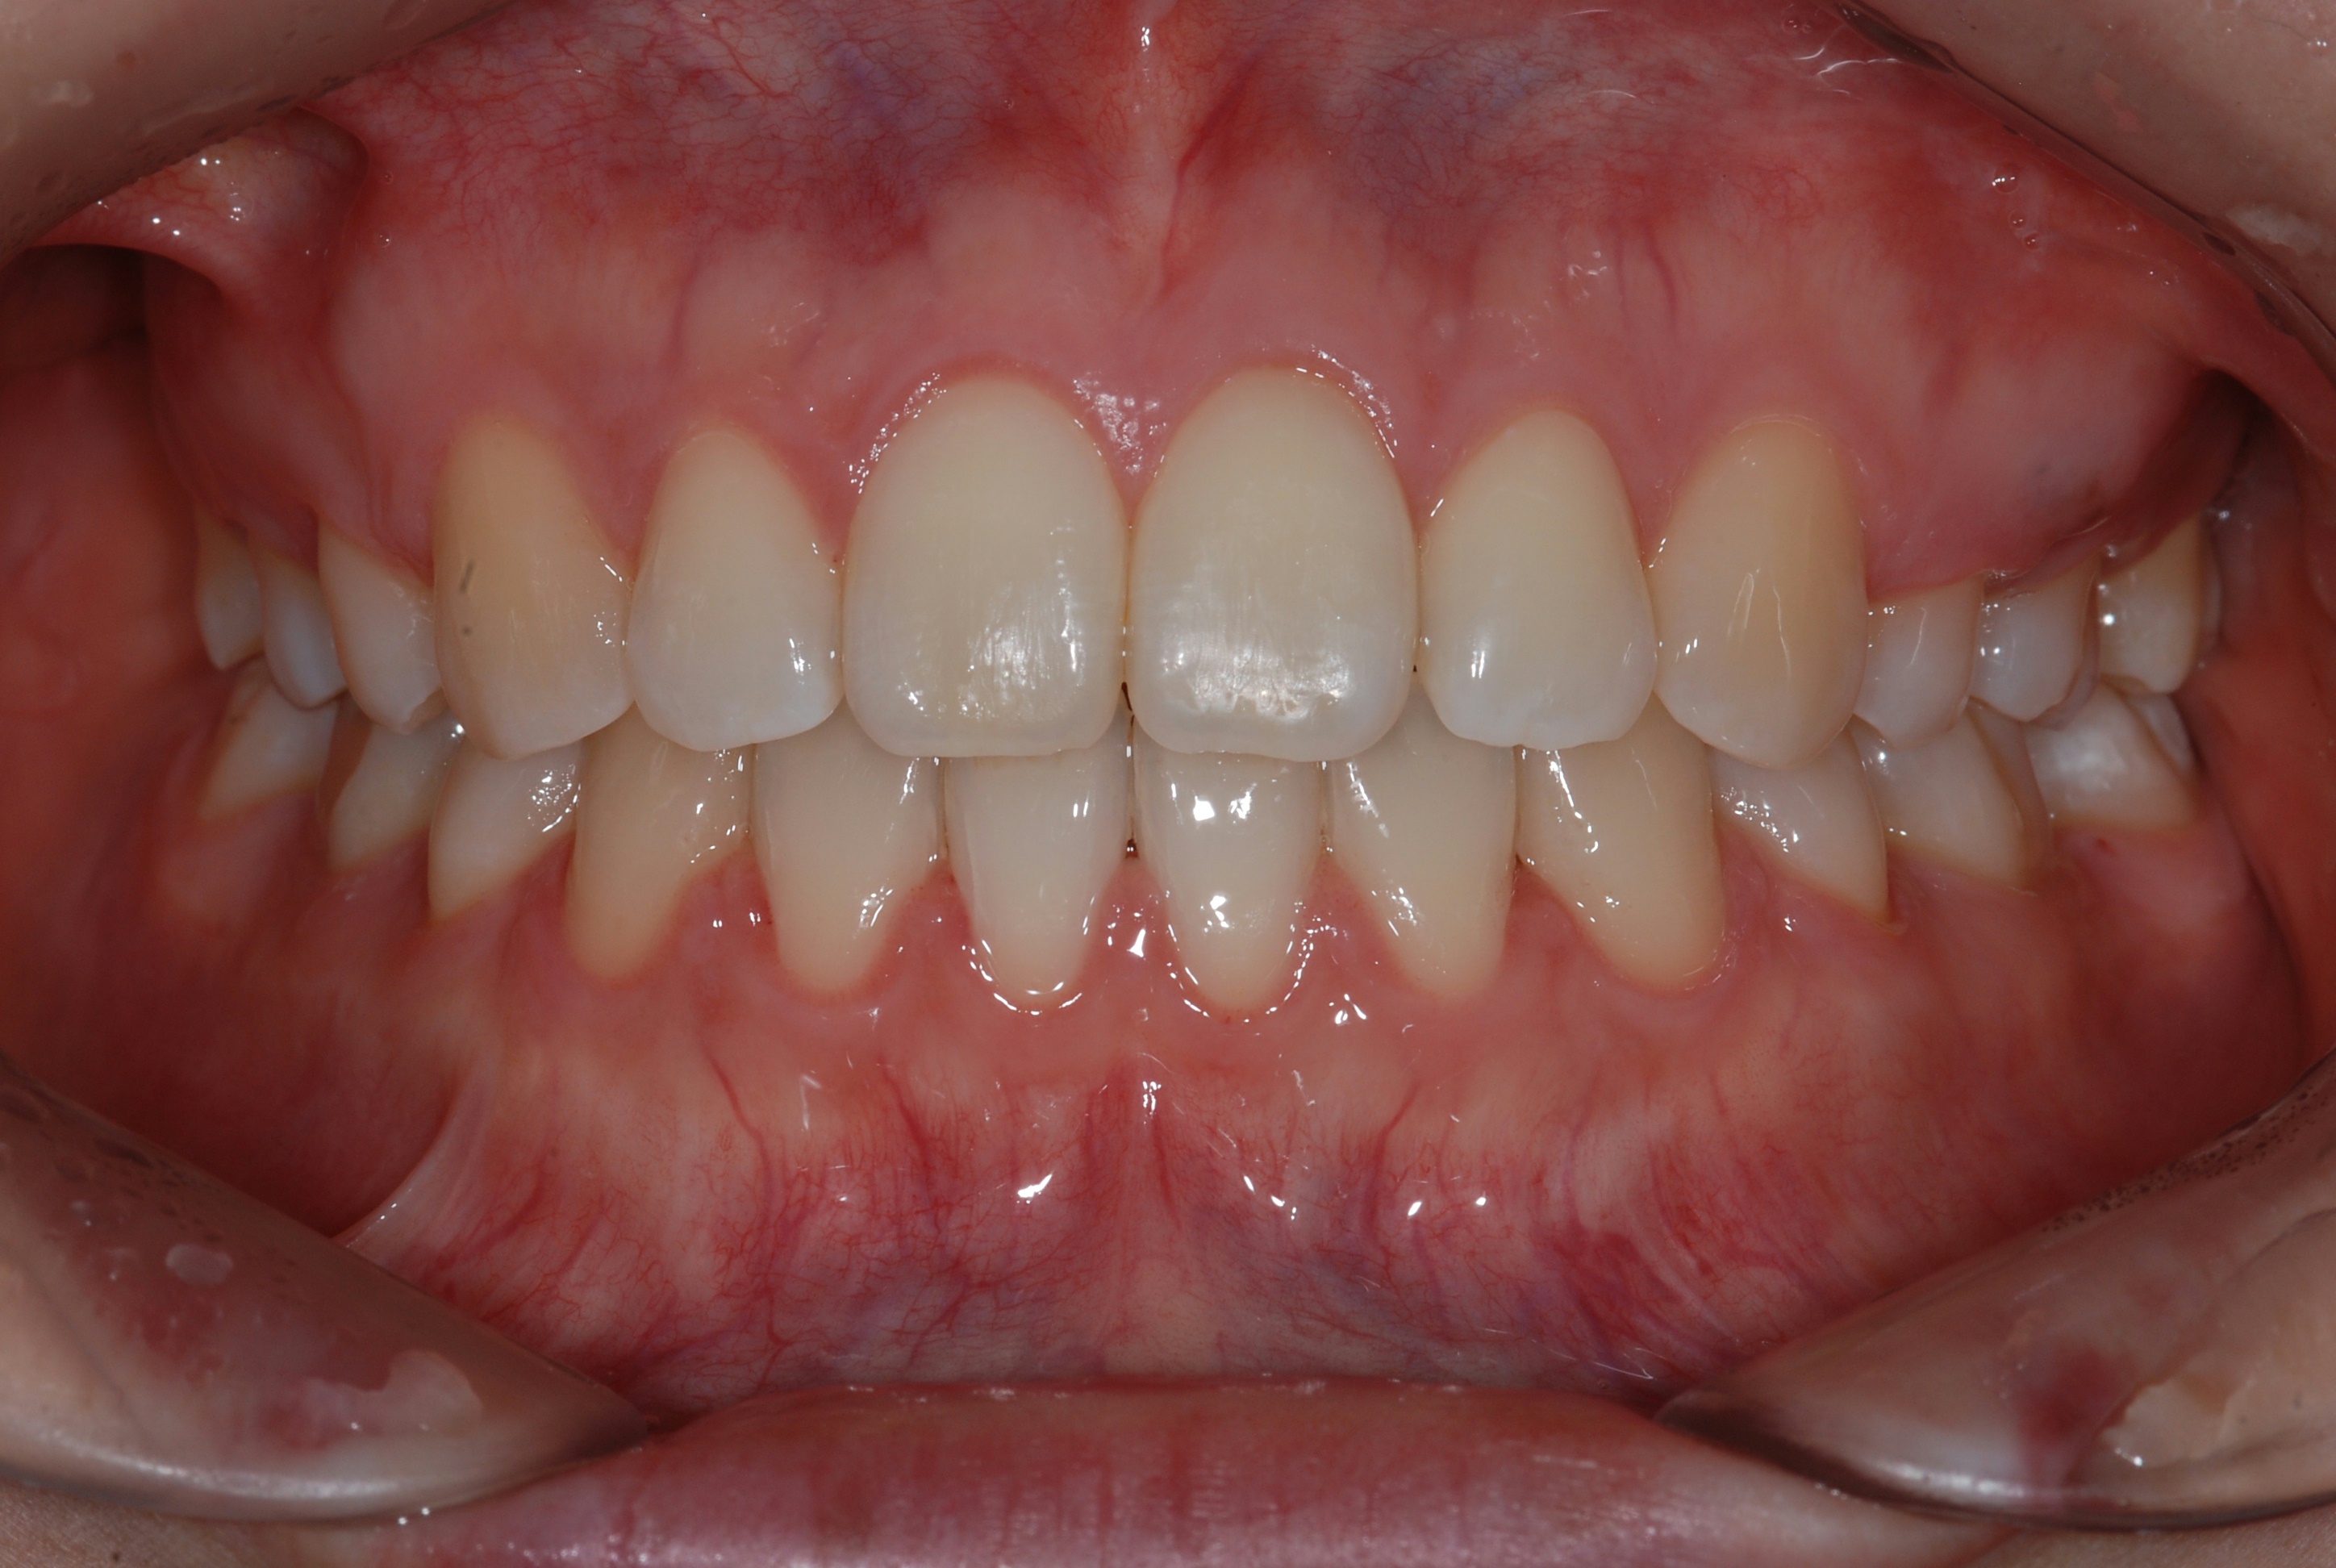

치료 후 사진입니다.